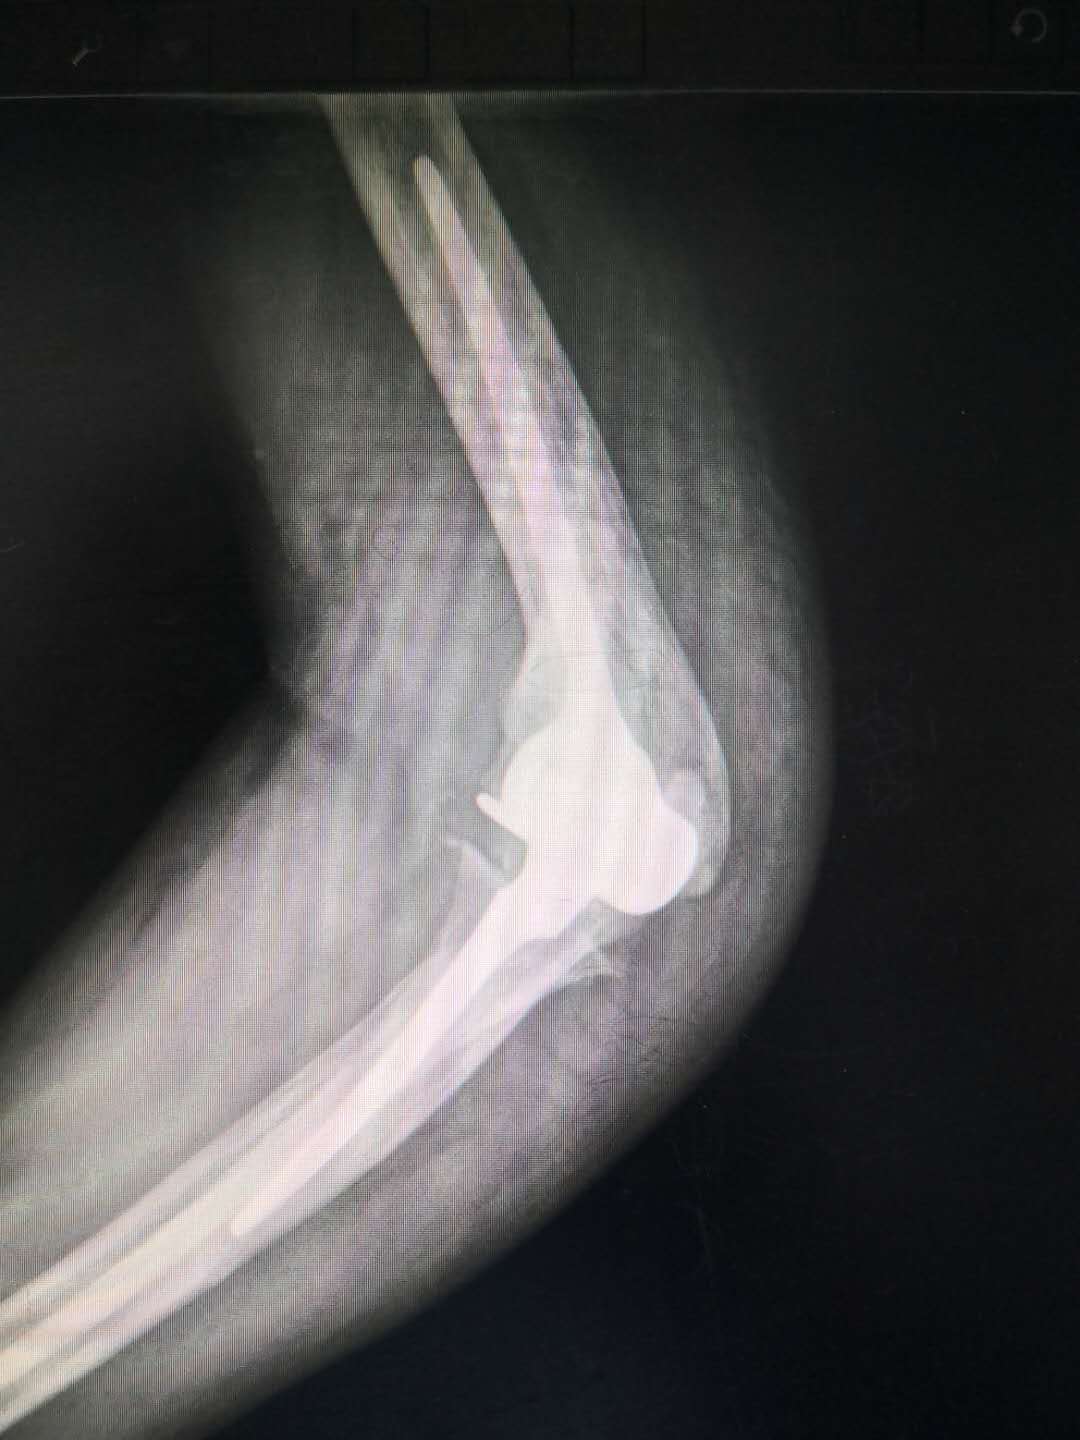

人工肘关节置换术